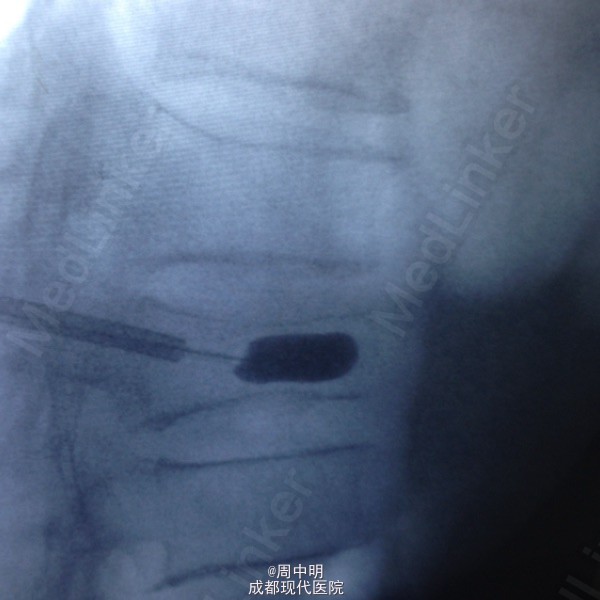

87岁,男性,T11压缩骨折

胸椎11压缩骨折